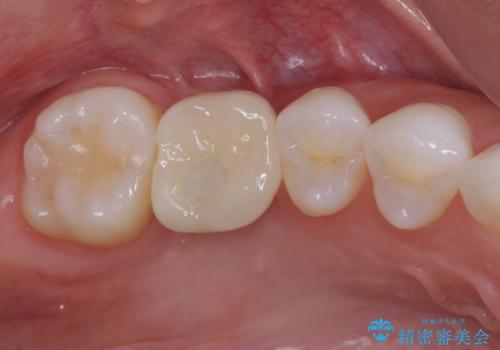

その後は、オールセラミッククラウンにて補綴することとしました。

虫歯を放置した期間が長かったため、対合の下顎大臼歯が上顎に迫ってきており、咬み合わせは非常にシビアでした。

仮歯装着中に頻繁に脱離したため、オールセラミッククラウンは脱離の少ないスクリュータイプとしました。